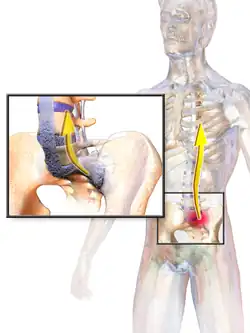

AS can occur in any part of the spine or the entire spine, often with pain localized to either buttock or the back of the thigh from the sacroiliac joint. Arthritis in the hips and shoulders may also occur. When the condition presents before the age of 18, AS is more likely to cause pain and swelling of large lower limb joints, such as the knees.[13] In prepubescent cases, pain and swelling may also manifest in the ankles and feet where heel pain and enthesopathy commonly develop.[13] Less common occurrences include ectasia of the sacral nerve root sheaths.[14]

Prognosis is related to disease severity.[11] AS can range from mild to progressively debilitating and from medically controlled to refractory. Some cases may have times of active inflammation followed by times of remission resulting in minimal disability while others never have times of remission and have acute inflammation and pain, leading to significant disability.[11] As the disease progresses, it can cause the vertebrae and the lumbosacral joint to ossify, resulting in the fusion of the spine.[44] This places the spine in a vulnerable state because it becomes one bone, which causes it to lose its range of motion as well as putting it at risk for spinal fractures. This not only limits mobility but reduces the affected person's quality of life. Complete fusion of the spine can lead to a reduced range of motion and increased pain, as well as total joint destruction which could necessitate a joint replacement.[45]

Osteoporosis is common in ankylosing spondylitis, both from chronic systemic inflammation and decreased mobility resulting from AS. Over a long-term period, osteopenia or osteoporosis of the AP spine may occur, causing eventual compression fractures and a back "hump".[46] Hyperkyphosis from ankylosing spondylitis can also lead to impairment in mobility and balance, as well as impaired peripheral vision, which increases the risk of falls which can cause fracture of already-fragile vertebrae.[46] Typical signs of progressed AS are the visible formation of syndesmophytes on X-rays and abnormal bone outgrowths similar to osteophytes affecting the spine. In compression fractures of the vertebrae, paresthesia is a complication due to the inflammation of the tissue surrounding nerves.